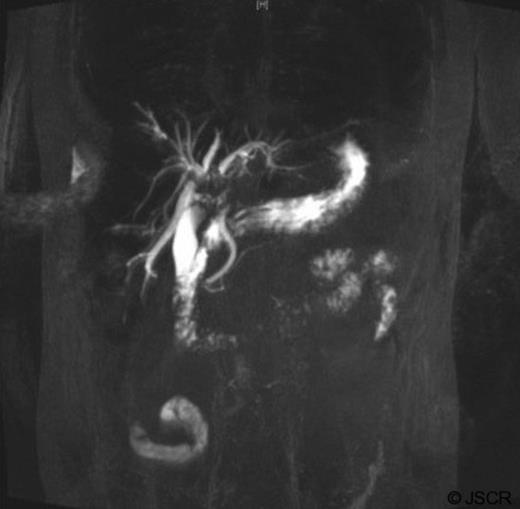

Over the next few months, the man was admitted for repeated cholangitis episodes. ERCP now indicated intra-hepatic duct filling defects (figure 4) and sediment was removed with new stents placed. Repeat abdominal-CT scans indicated the mass was similar in size. Following these presentations, the multidisciplinary team decided to undertake laparoscopic liver biopsy.